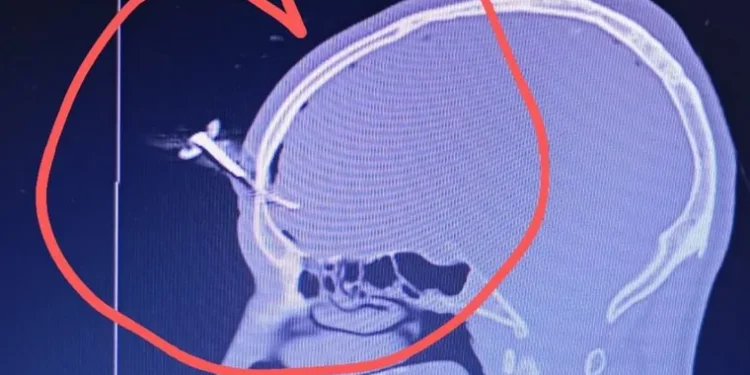

El hecho ocurrió en la noche del miércoles en el club barrial GEVE, ubicado en Avenida Italia y 150, cuando una discusión entre padres de jugadoras derivó en una confrontación generalizada. Según fuentes policiales, Smith intervino para defender a un amigo que estaba siendo golpeado y terminó siendo atacado con una llave que quedó incrustada en su frente.

La gravedad de la lesión obligó a los profesionales del Evita Pueblo a solicitar asistencia al Hospital El Cruce de Florencio Varela, centro de alta complejidad desde donde se coordinaron las indicaciones para la extracción de la llave.